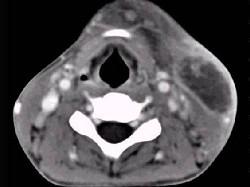

问题 男性,67岁,颈部出现疼痛性肿块半年余,CT扫描如图所示,最可能的诊断是 ( )

选项 A、淋巴瘤 B、血管瘤 C、囊肿 D、淋巴结核 E、神经鞘瘤

答案 A